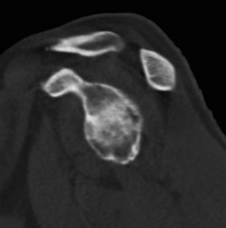

Type A2 Type B1

Type B2 Type B3

Type B3